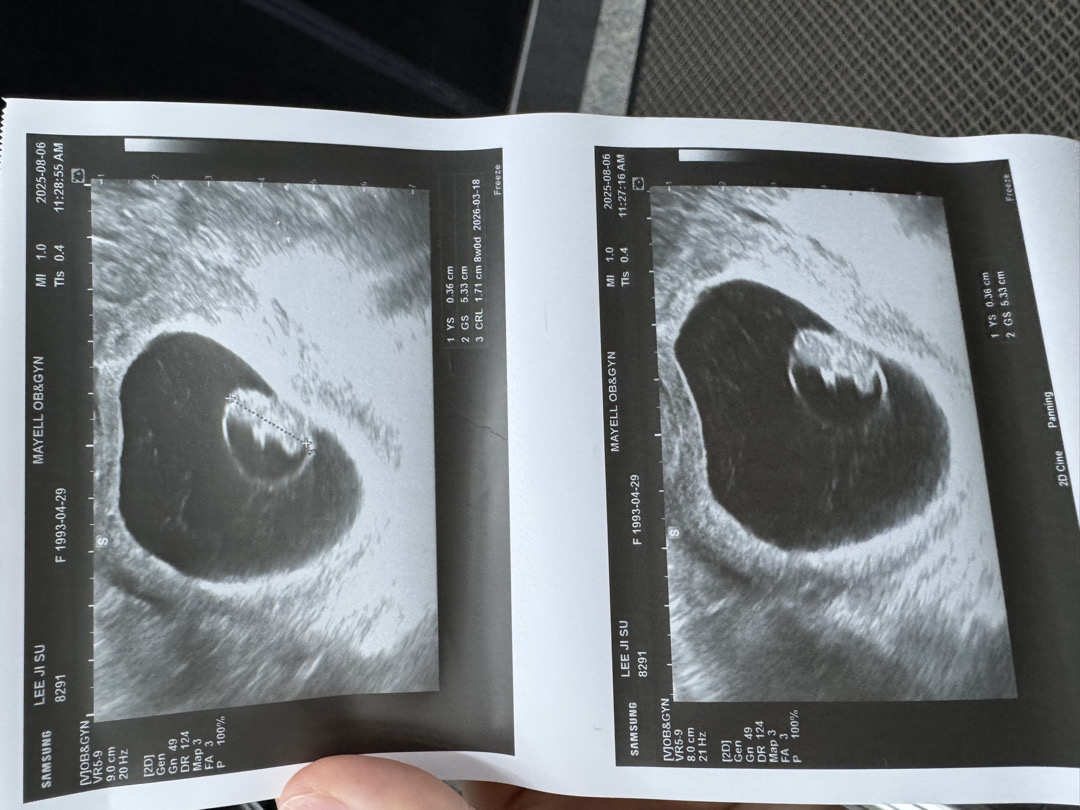

8주3일차 초음파보고왔어요

애기주변에 하얀띠가 뭥가 했더니 양막이라고 하더라구요 넘 신기해요-! 8주차 들어서면서 입덧이 확실히 심해진 느낌이에요. 계속 약간 울렁거리는 느낌 토는 안하지만 헛구역질은 계속 합니다 ㅠㅠ